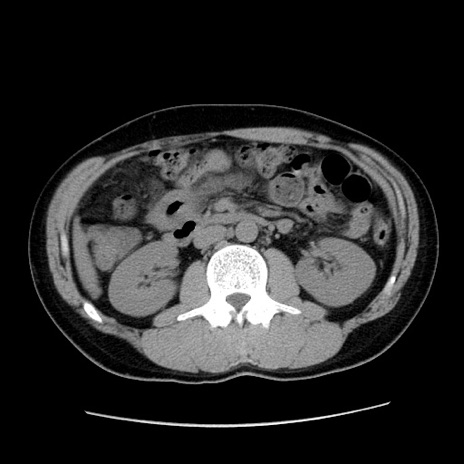

冠状断像

【症例】20歳代 男性

【主訴】心窩部痛

【現病歴】今朝より上腹部痛あり。一旦軽快していたが再度出現したため救急要請。昨日夕に白身の魚を含む刺身を食べた。

【身体所見】BP 136/89mmHg、HR 74/min、BT 37.0℃、腹部:膨満、軟、心窩部に圧痛あり。反跳痛なし、筋性防御なし、腸雑音やや亢進あり。

【データ】WBC 17700、CRP 0.48